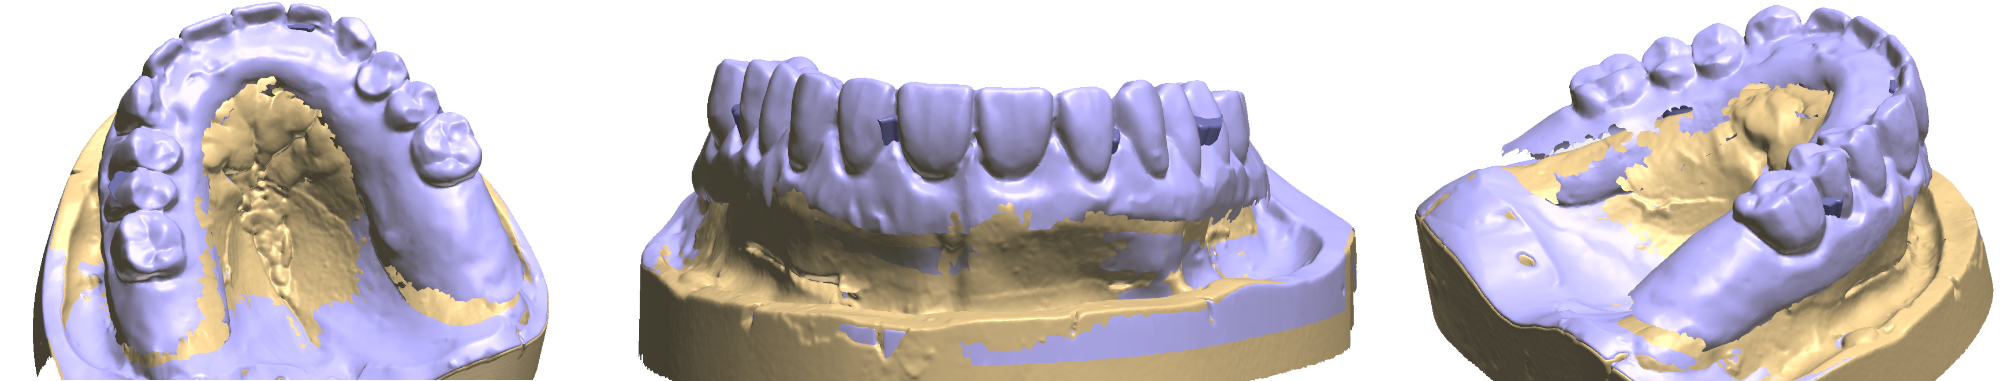

Teleskopierende Brücken im digitalen Ablauf hergestellt.